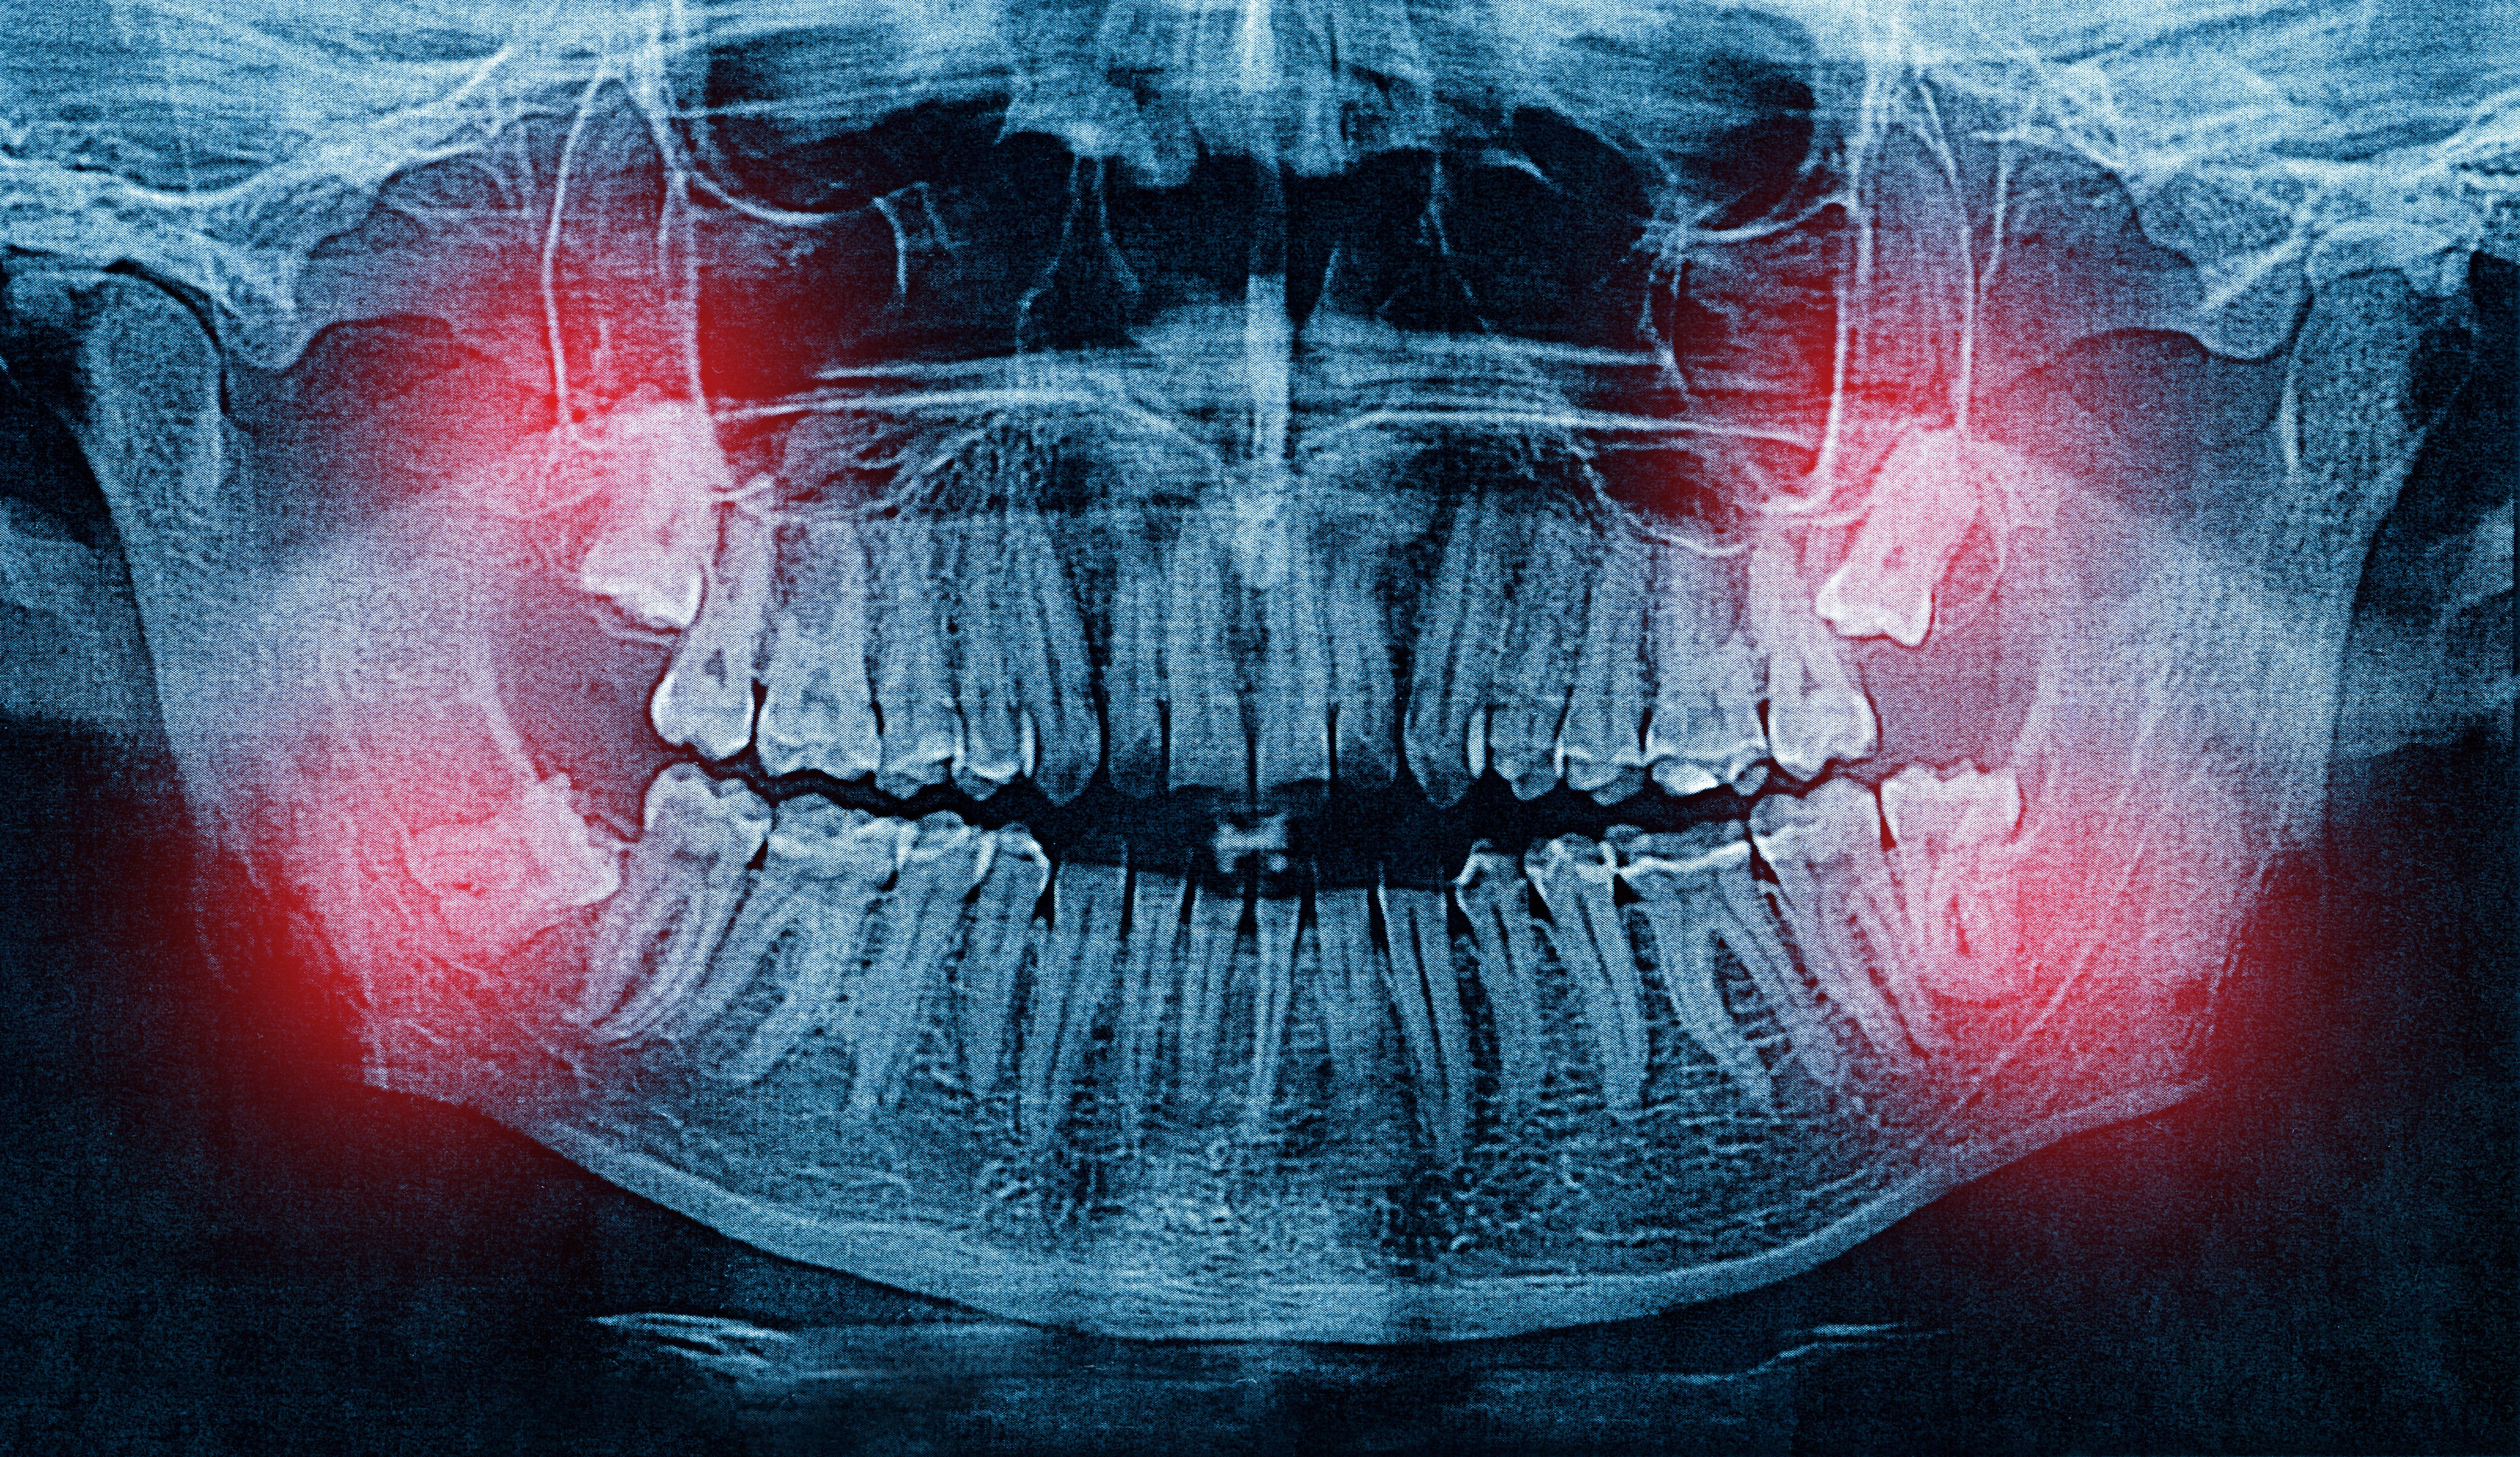

At Jennifer Lopez Dental in Miami, Dr. Lopez uses CBCT cone beam imaging to see the exact position of your wisdom teeth relative to nerves, sinuses, and adjacent roots. This detailed 3D view allows her to plan the removal with greater safety, accuracy, and efficiency than traditional X-rays alone. The procedure is performed under local anesthesia, and most patients return to their normal routine within three to five days.

3D imaging maps the exact position of each wisdom tooth relative to nerves, allowing Dr. Lopez to plan removal with precision.

Dr. Lopez evaluates your wisdom teeth with 3D CBCT scans to assess their position, root development, and proximity to nerves — ensuring the safest approach for removal.